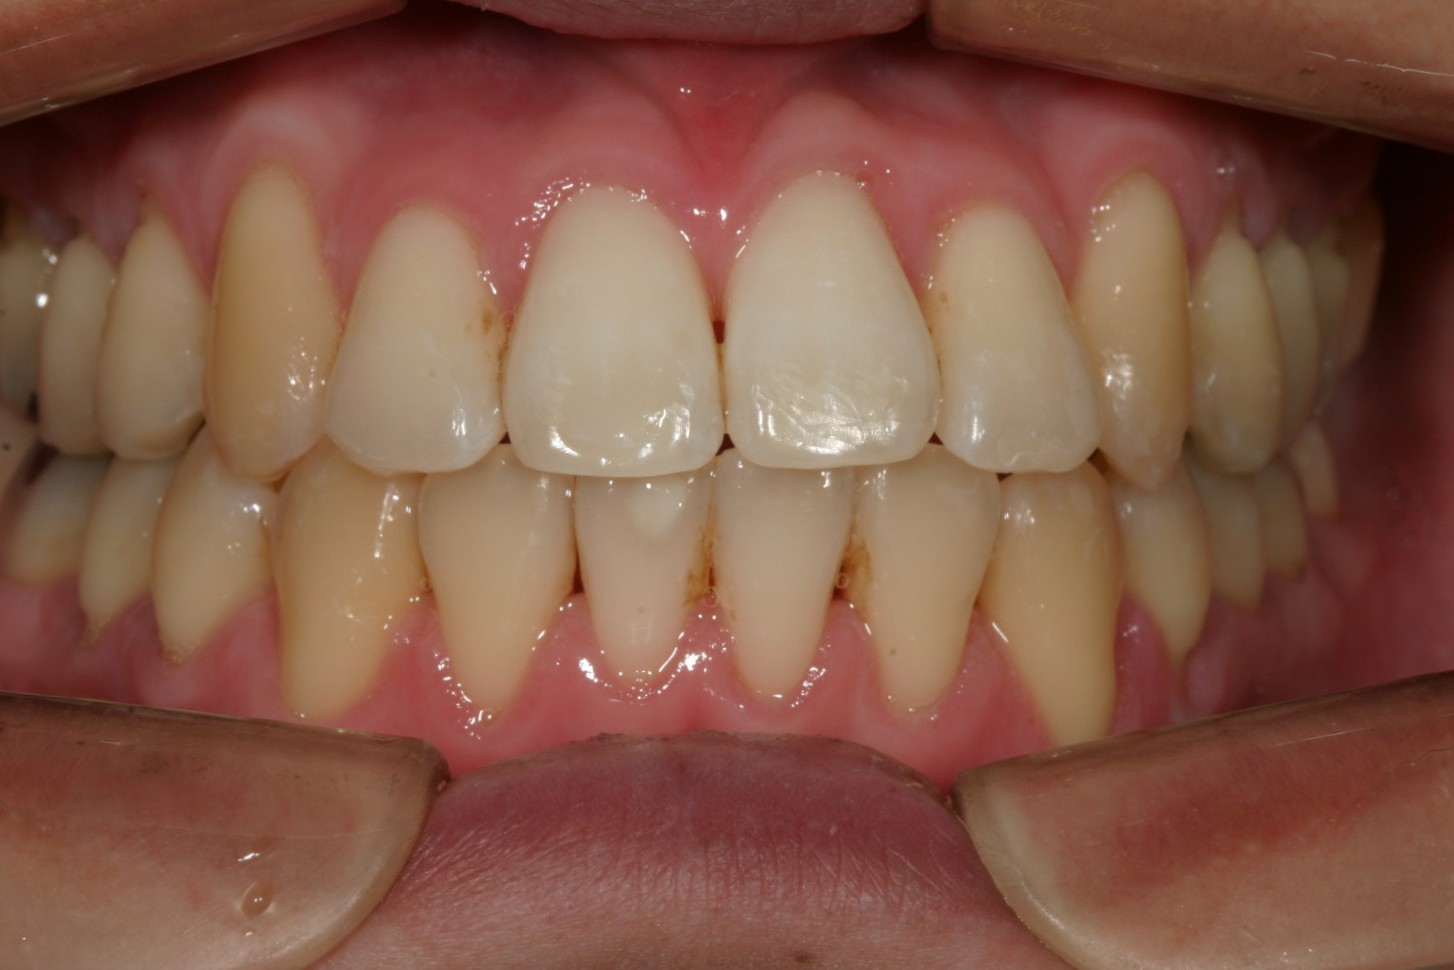

かなり綺麗になって来ました。

11か月後です。 綺麗なアーチに改善しました。

下顎のアーチも広がり綺麗になりました。

側面観も綺麗ですね~